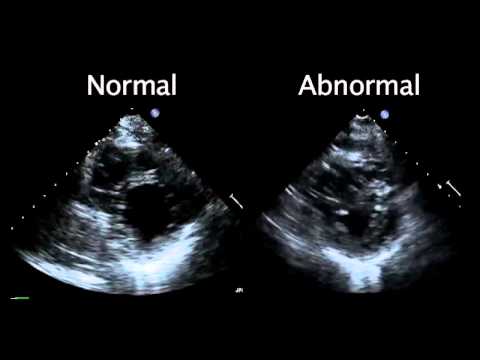

Doctor explains Echocardiogram Heart Test | Everything you need to know

Echocardiogram from the Patient Compared with That from a Normal Control | NEJM